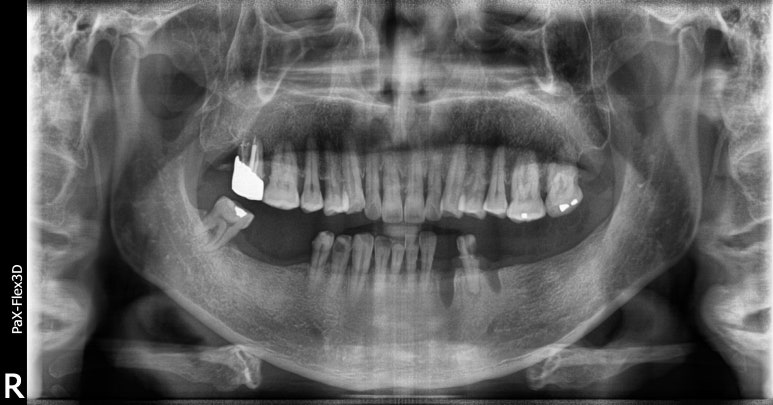

68세 남성

보험임플란트

(전) 2021-11-05 (후) 2022-08-18

만 65세 이상으로 국가에서 금액을 일부 지원하는 보험임플란트를 진행하신 환자분입니다.

치아가 상당 부분 결손되어 있어 생활하시는데 불편함이 많으셨을텐데, 임플란트 시술 후 씹는 즐거움을 되찾을 수 있었습니다.

상실된 치아를 방치하게 되면 치아가 조금씩 이동해 치아 배열이 망가지고 임플란트 식립이 어려워질 수도 있습니다.

따라서 빠르게 치과에 방문하셔서 치료받으시는 것이 가장 좋습니다.